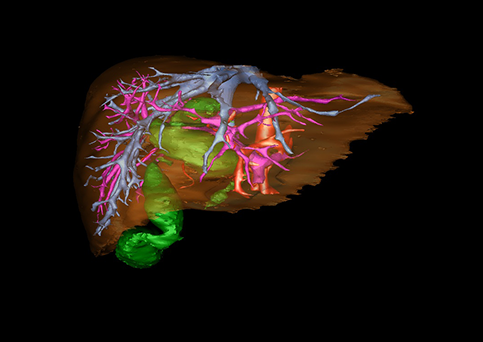

10、三维重建虚拟肝脏、胆道显像技术

三维虚拟肝脏技术是在二维影像学资料如CT等图像的基础上,通过三维重组软件和工具,比如青岛大学附属医院与海信医疗集团联合自主研发的海信计算机辅助手术系统(Hisense Computer Assisted Surgery,Hisense CAS),目前已投入临床并指导实际应用,利用该类系统对二维影像学的数据资料进行三维立体分析,重组形成立体的、有空间结构的、虚拟的肝脏三维图像。这项技术较传统的二维平面成像技术,有着明显的优势,3D虚拟肝脏技术可以构造出一个虚拟的、可视化的肝脏模型。通过对这种模型的观察,可以很容易地分辨出肝脏器官的组织结构、解剖特点,直观研究肝外胆总管的形态差异,明确肝内胆管的形态、走形、是否合并扩张、狭窄及结石,胰胆管合流的形态及共同通道内是否有狭窄、扩张和结石等病变情况,预先规划处理可能合并存在的肝内胆管扩张、狭窄或其他复杂胆道畸形,清晰地显示肝内脉管系统,包括门静脉、肝动脉及肝静脉的走行、分支,并可多角度、全方位观察病变胆道与其周围重要血管尤其是伴行的门静脉之间的解剖关系,大大提高了外科医师在术前对肝脏内部各管道结构及其变异判断的精确性和可靠性,精准地对病变进行判断和评估,还可根据患者自身的病变特点,制定出合理、个体化的手术方案,最大限度地降低术中和术后并发症发生率,并术中导航实时指导手术,提高手术的精准性和成功率。

图10:先天性胆管扩张症囊肿型三维重建虚拟肝脏、胆道显像

a 图为术前二维CT扫描图像,箭头所示为肝内胆管扩张;b 图为CT经多平面重组技术(MPR)图像后处理所得的重建图像,可显示胆总管明显扩张合并肝内胆管扩张;c 图为MRCP显示胆总管呈囊柱状扩张,直径>1 0 cm,伴肝内胆管扩张;d 图示Hisense CAS三维重建清晰显示肝脏、胆道系统及其与门静脉、肝动脉、肝静脉等之间的空间解剖关系;e 图示Hisense CAS可从任意角度以不同脏器组合显示,明确胆道系统与其伴行的门静脉系统的空间解剖关系;f 图示胆道系统立体形态及与肝脏整体的空间关系,箭头处显示肝内胆管狭窄部位发生于左右肝管汇入肝总管处。术前规划需行肝内胆管扩大成形术。